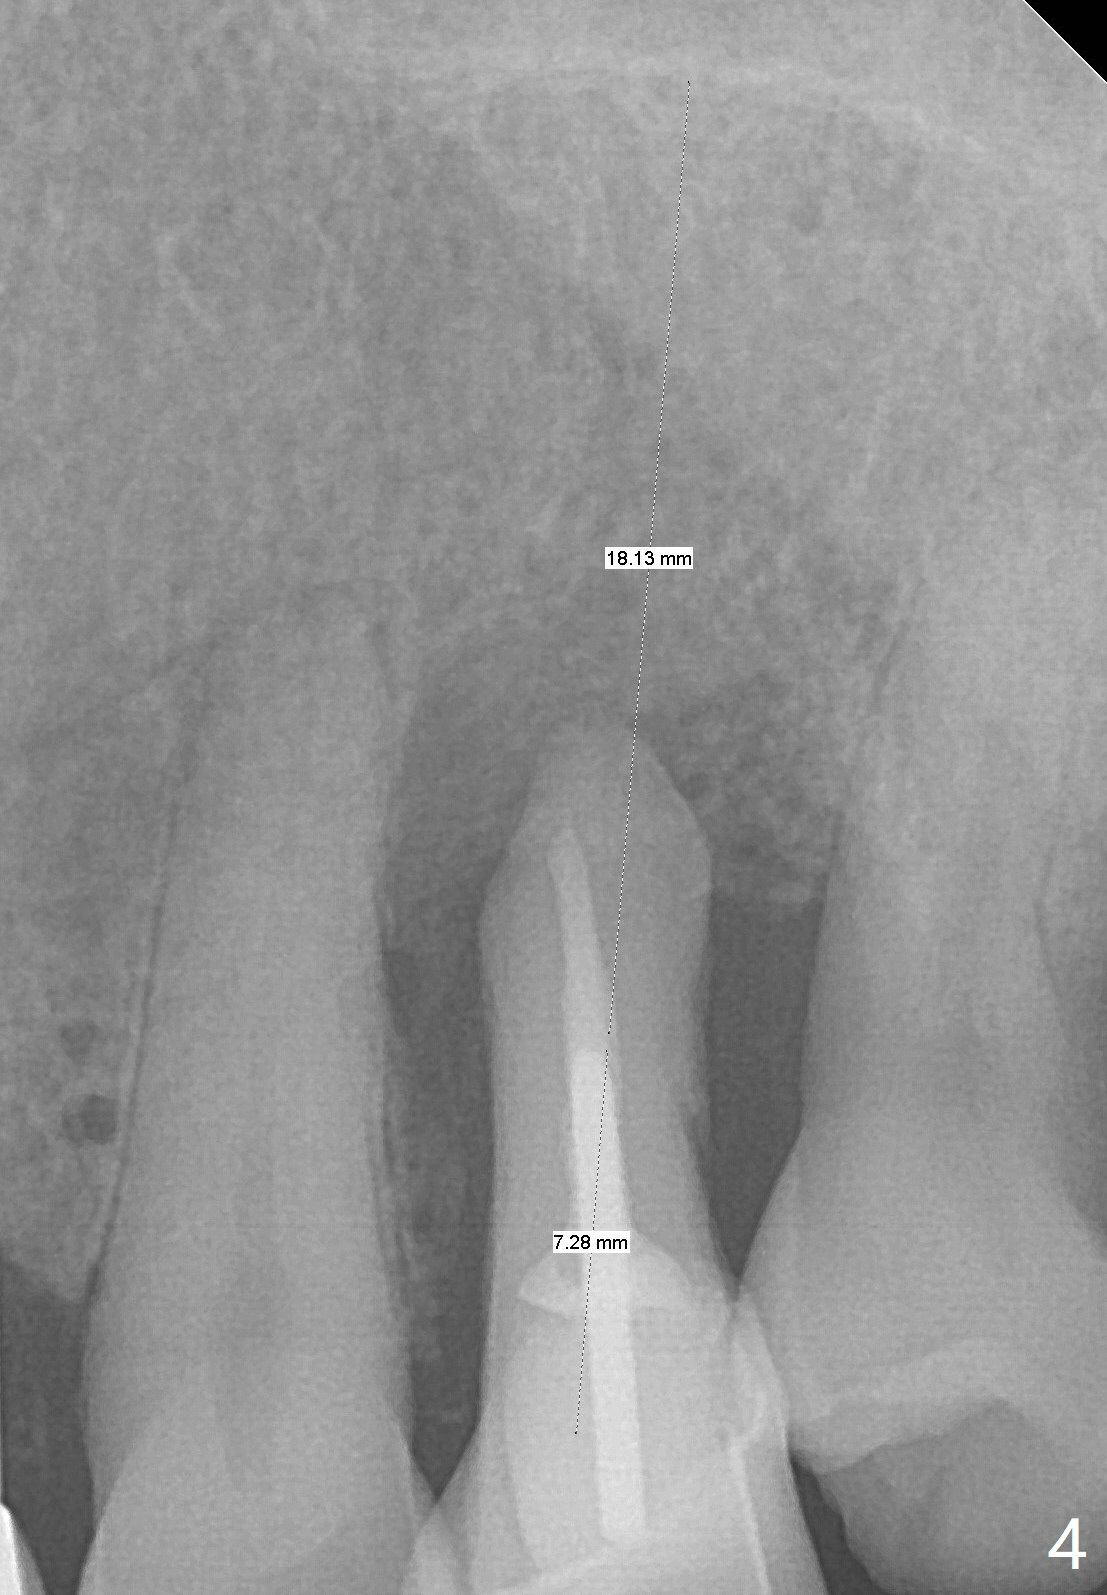

A 61-year-old man with chronic periodontitis presented to clinic for several implant placement (#3 10 14/15 18 30). For the tooth #12 (Fig.1), RCT was rendered (Fig.2). The tooth is non-salvageable 4.5 years post-treatment (Fig.3). Uneven bone loss mesiodistally makes implant placement challenging (Fig.4). A long implant will be used with ~3 mm subcrestal (mesially) and ~3 mm supracrestal (distally). A 3.5 or 4.0x13 mm implant will be placed subcrestal palatally and supracrestal buccally (Fig.5).